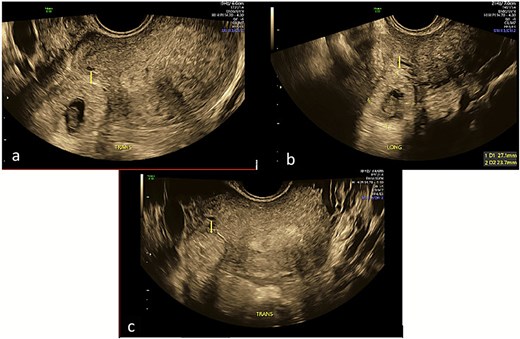

Repeat specialist ultrasound (Fig. 1) identified a right interstitial ectopic pregnancy measuring 27 × 24 × 26 mm, with a decidual reaction, a foetal pole and absent cardiac activity. The gestational sac did not communicate with the endometrial cavity. Diffuse cystic adenomyosis was noted (Fig. 2). Retrospective review indicated that sub-endometrial microcysts had been mistaken for a gestational sac on earlier scans (Fig. 3).

Transverse and longitudinal views of the uterus on trans-vaginal ultrasound demonstrating a right interstitial ectopic pregnancy with gestational sac and foetal pole. Image A demonstrates a decidual reaction around the gestational sac in a transverse plane through the uterus. Image B measures the gestational sac in the longitudinal plane. Image C demonstrates that the pregnancy does not communicate with the endometrial cavity in a transverse plane through the uterine fundus.

Interstitial pregnancies may be difficult to diagnose even under optimal conditions. Key diagnostic features, including the interstitial line sign and absence of communication with the endometrial cavity, were clearly visualised only upon specialist ultrasound assessment (Fig. 1), underscoring the importance of high-resolution imaging and expertise.